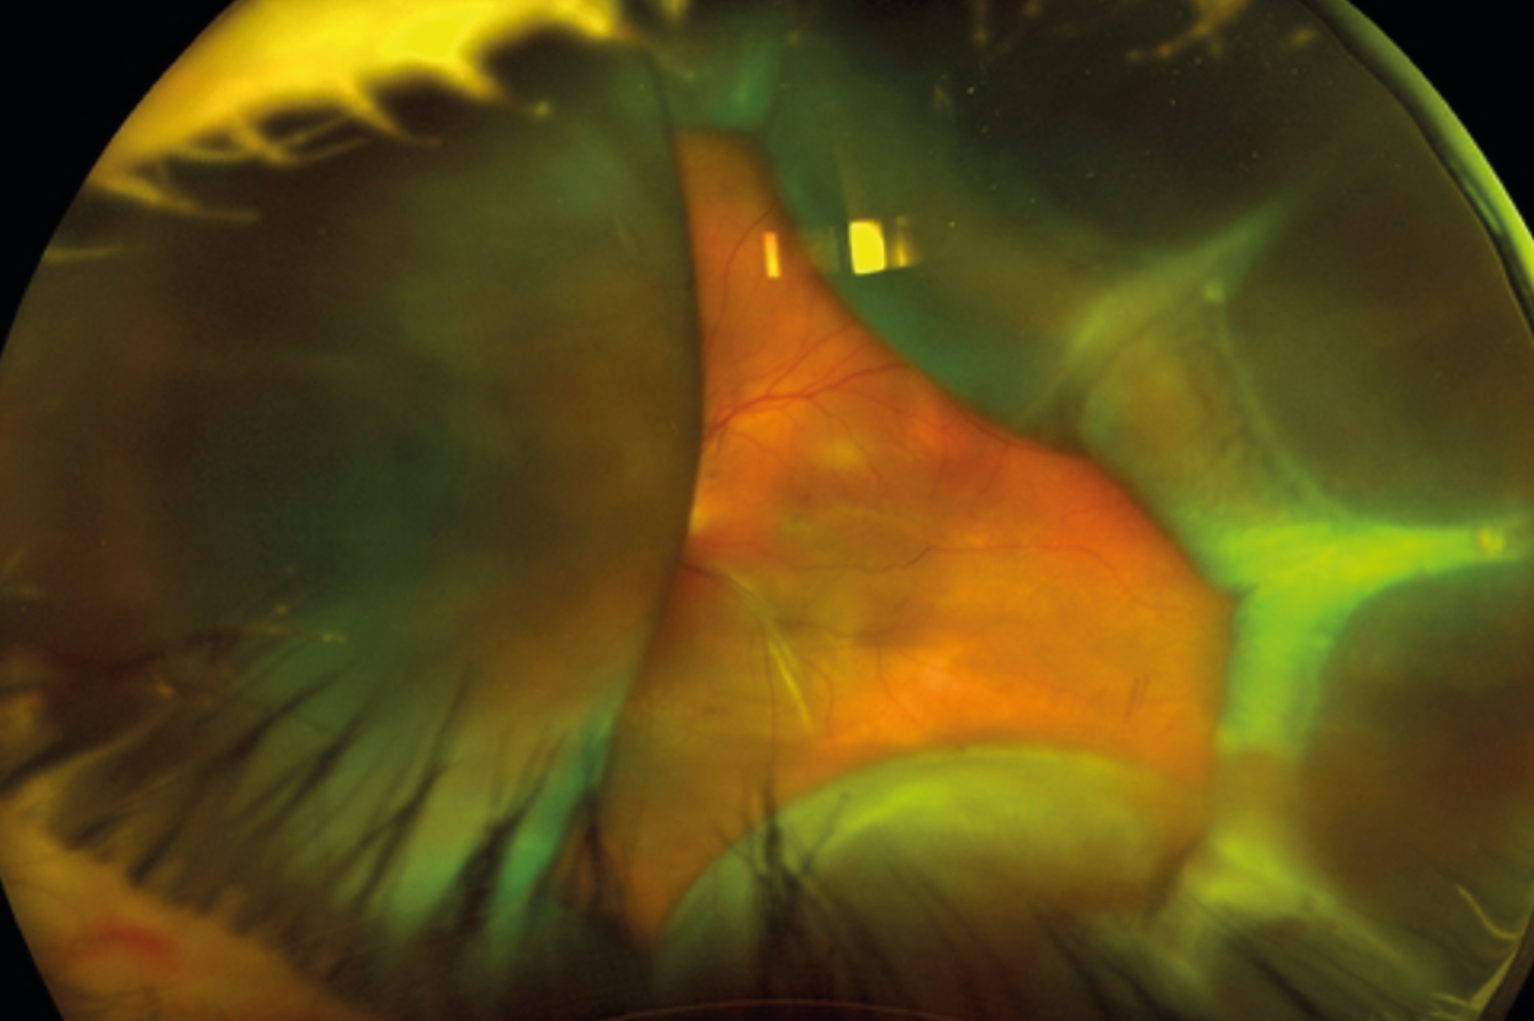

Le diagnostic d’un glaucome et son suivi peuvent se révéler difficiles chez les sujets myopes forts du fait de l’aspect trompeur de la papille optique et des différentes altérations des structures du segment postérieur, des conséquences de la myopie sur le champ visuel et des difficultés d’analyse de l’OCT. La prise en charge de cette forme de glaucome à angle ouvert repose sur l’abaissement de la pression ­intraoculaire, avec peu de spécificités par rapport à un glaucome primitif à angle ouvert classique, le traitement médical étant souvent utilisé en première intention.

La chirurgie peut être envisagée en présence d’un glaucome évolutif sous traitement médical maximal et du risque de perte du point de fixation ou d’intolérance aux collyres.

La réalisation est souvent plus difficile que chez les non myopes car les repères ­anatomiques habituels sont fréquemment modifiés ou absents.

En cas d’hypotonie postopératoire, les risques de complications telles qu’un soulèvement choroïdien ou un œdème maculaire sont importants chez les sujets myopes forts et nécessitent un suivi très régulier ainsi qu’une prise en charge adéquate le cas échéant.